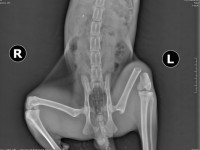

In urma consultului medical, pe langa ranile deschise de la bot si de la una din labele din fata, a reiesit ca are si o fractura de femur, asa cum se poate vedea din radiografie. Este suspect si de o fractura la una din labele anterioare, insa de asta ne-am dat seama destul de tarziu si abia luni ii vom face radiografia pentru confirmare.

After he was examined, beside his wounds to his face and one of his paws, he also had a fractured femur, as you can see on the x-ray. He could also have broken front paw, but that can only be confirmed monday.